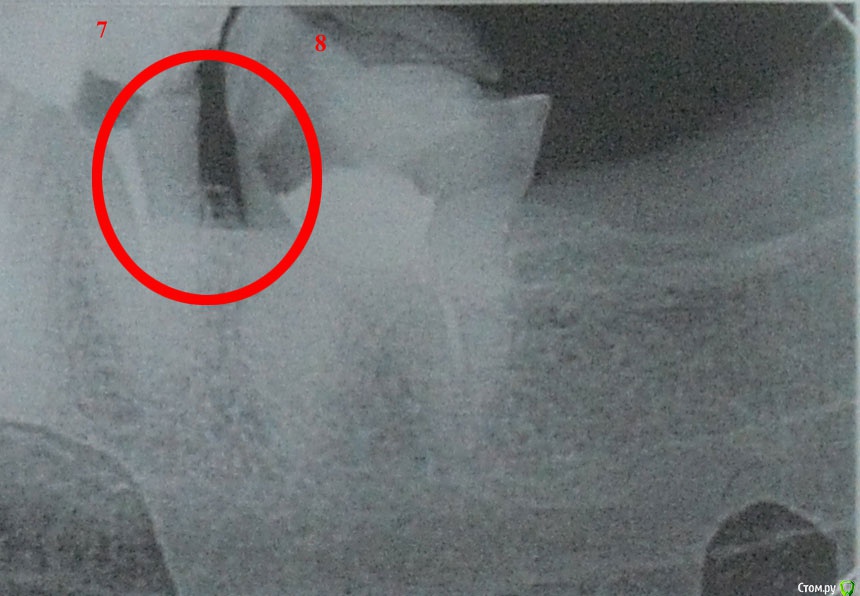

usersha Опубликовано 6 августа, 2019 Автор Поделиться Опубликовано 6 августа, 2019 уважаемые доктора подскажите пожалуйста насчет флюса? неужели такие проблемы с лечением флюса? что же теперь десна воспалилась и только зубы рвать? Зуб мудрости у меня не болит! Неужели без удаления никак? там действительно по рентгену карман? Подскажите пожалуйста уважаемые доктора! И еще момент хирург предлагает в качестве анастезии убистезин! говорит что он лучше обезболивает а так как идет воспалительный процесс то лидокаин с адреналином могут плохо подействовать и будет больно! Я постоянно принимаю анаприлин, он нормально сочетается с убистезином? раньше мне кололи лидокаин садреналином и я нормально переносила. Что скажете про убистезин, заранее большое спасибо! Ссылка на комментарий

red_butler Опубликовано 6 августа, 2019 Поделиться Опубликовано 6 августа, 2019 Про зубы я Вам ответил. Карман есть. Убистезин нормальный препаратP.s. Надеюсь дизлайк Вы мне поставили ошибочно... Ссылка на комментарий

usersha Опубликовано 6 августа, 2019 Автор Поделиться Опубликовано 6 августа, 2019 Про зубы я Вам ответил. Карман есть.Убистезин нормальный препаратP.s. Надеюсь дизлайк Вы мне поставили ошибочно...нет не ошибочно! вы конечно модератор администратор и можете легко забанить меня! но я все равно скажу! вы не отвечаете по существу! за это и минус! я спросила насчет флюса и его лечения без удаления 8 зуба! все что вы советуете только удалять! причем здоровый зуб! и насчет анастезии я спросила как он совместим в анаприлином! вы отвечаете нормальный препарат! прерасный ответ! в инстукции к убистезину написано противопоказание и несовместимость с неселективными бета-блокаторами а анаприлин как Вам известно это неселективный бета блокатор! поэтому я и спрашивала! и еще меня интересовала это действительно так что лидокаин с адреналином при воспалительном процессе плохо действуют и что при тех же условиях то есть воспалении убистезин действительно лучше действует? я спросила про карман потому что во первых мне никогда пища в межзубном пространстве не застревала! во вторых есть истиные и ложные карманы! в третьих мне ни один из врачей не проверил то есть не зондировал десну чтобы говорить карманы! и наконец по снимку видно что одна и таже часть сильно отличается ! я не спец но видела снимки в сети карманов где идет разрушение кости или как там правильно называется! у меня на одном снимке между зубами четко видна белая полоса а на другом нет! может принтер УДАЛЕНО АДМИНИСТРАТОРОМ в поликлинике как может отличаться одна и таже часть на снимках! вы конечно извините меня за резкость но меня достало что к нам относятся как быдлу! я знаю что на этом форуме мне никто ничего не должен! у нас в этой стране никто уже никому ничего не должен,дальше я помолчу иначе тема сведется к политике. 1 3 Ссылка на комментарий